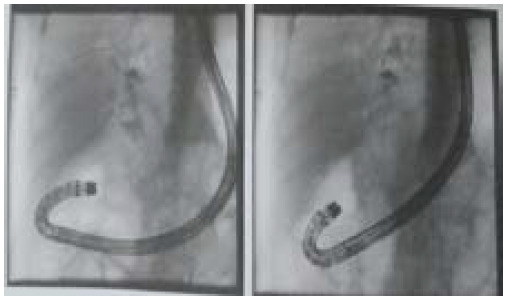

胆总管十二指肠瘘是胆总管与十二指肠之间的异常连接。最常见的原因是胆囊结石,然而,其他原因是医源性因素,胆管结石(胆总管结石),和慢性十二指肠溃疡。在此,我们报告一例胆囊切除术后继发于长期胆总管结石的胆总管十二指肠瘘,在过去的三年里,他表现出间歇性腹痛,并在内镜下逆行胆管造影时发现胆总管十二指肠瘘。由于患者复发性疼痛并伴有胆总管结石,需要手术治疗。胆管炎复发疑为胆总管十二指肠瘘,难治性和复杂性病例建议手术治疗。对于较大的瘘管,尤其是无法解决的药物治疗,也建议手术治疗。本病例强调胆总管结石合并胆总管十二指肠瘘的治疗选择。

Choledochoduodenal fistula is an abnormal connection between the common bile duct and the duodenum. The commonest cause is cholecystolithiasis, however, other causes are iatrogenic factors, bile duct stones (choledocholithiasis), and chronic duodenal ulcers. Here, we report a case of choledochoduodenal fistula secondary to long standing choledocholithiasis post cholecystectomy who presented with intermittent abdominal pain in the past three years which revealed choledochoduodenal fistula during Endoscopic Retrograde Cholangiopancreatography. As the patient had recurrent pain along with choledocholithiasis, surgical intervention was indicated. Choledochoduodenal fistula is suspected in case of recurrent cholangitis and surgery is recommended for refractory and complicated cases. Surgical treatment is also recommended for larger fistulas and especially with non-resolving medical treatment. This case highlights the treatment option for choledocholithiasis with choledochoduodenal fistula.